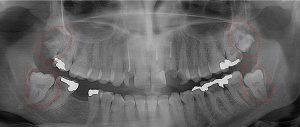

This 34 year old patient has all four third molars present (circled) and fully erupted into occlusion. They appear disease free…but are difficult to keep clean. 3rd molars are the most likely teeth to decay or have gum disease with a >98% probability that decay and gum disease will occur around all four teeth over this patient’s life time.